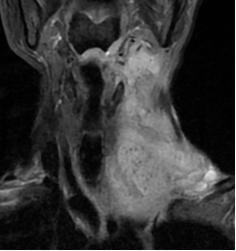

经保守治疗至第3天时,复查电子喉镜及颈部MRI检查后,提示病情无明显改善,并且咽喉会厌脓肿已形成并破溃流脓、颈深部脓肿形成,且范围大,炎症累及上纵膈边缘,脓肿一旦破入胸腔,死亡风险大大增加,病情相当危险,不能再耽搁。

告知患者及家属病情的凶险及严重后果后,谢云波副主任医师即刻评估病情,当天下午在急诊局麻下行颈部探查+颈部及咽旁脓肿切开引流术。

(术前MRI平扫+增强)